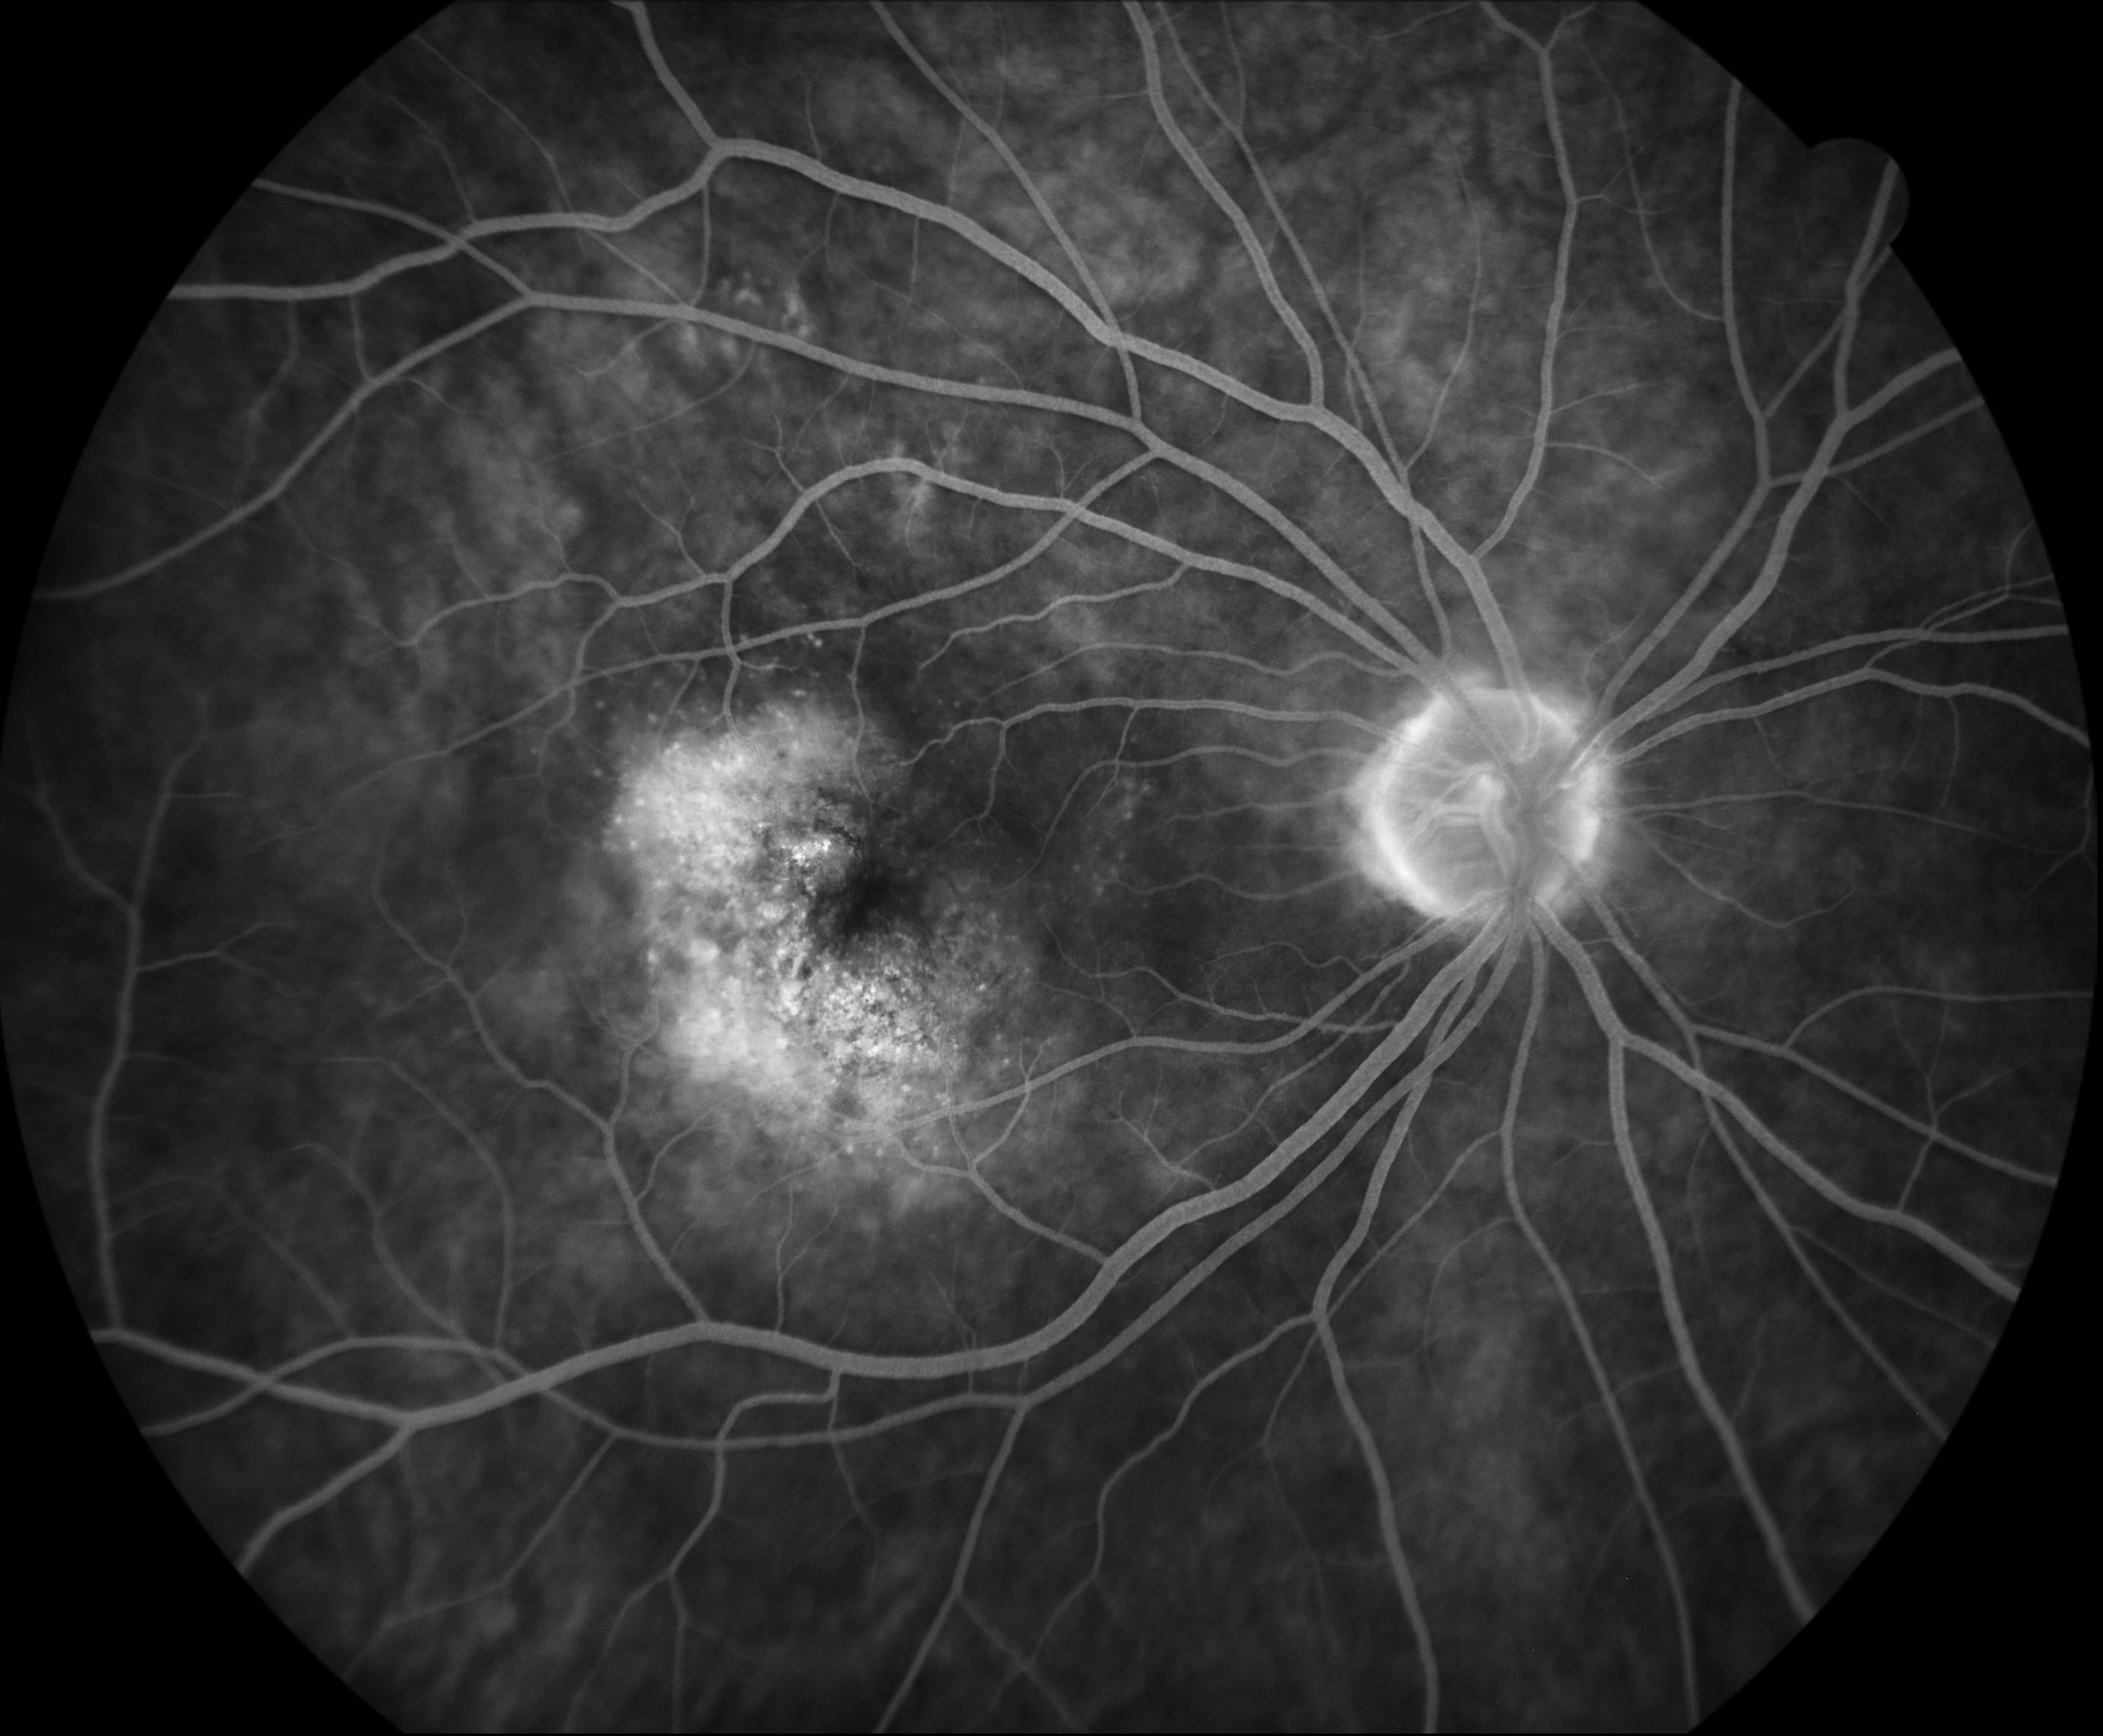

AMD Presented by Hayleena Cote, OCT-C, CRA This photograph received Third Place, Fluorescein Angiography (30° - 40°)in the 2025 OPS Scientific Exhibit. Filed Under Cornea OPS Photo